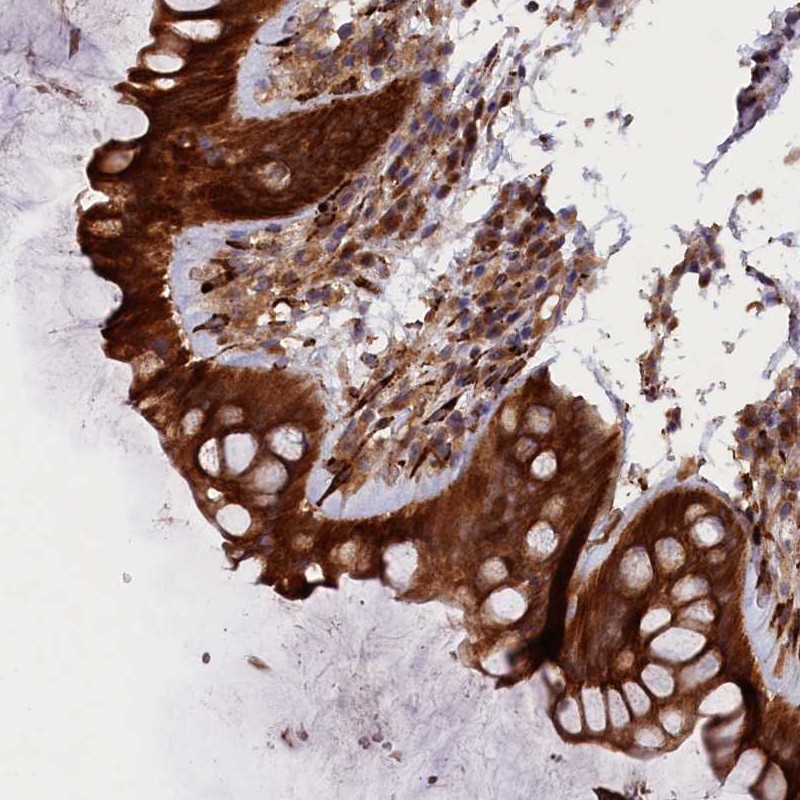

Immunohistochemical staining of human rectum shows strong cytoplasmic positivity in glandular cells.